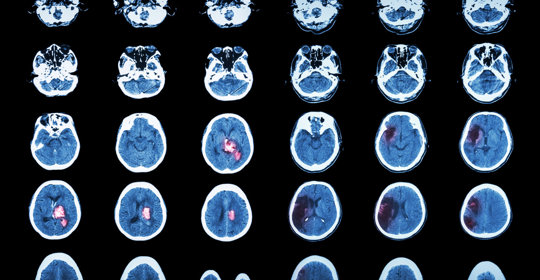

腦幹出血:顱內壓控制、生命支援、抗高血壓

腦幹出血:原因、症狀與治療

腦幹出血:原因與恢復

腦外傷:意識障礙、瞳孔異常、嘔吐、眩暈、呼吸不規則

腦幹出血:症狀、嚴重性與後遺症